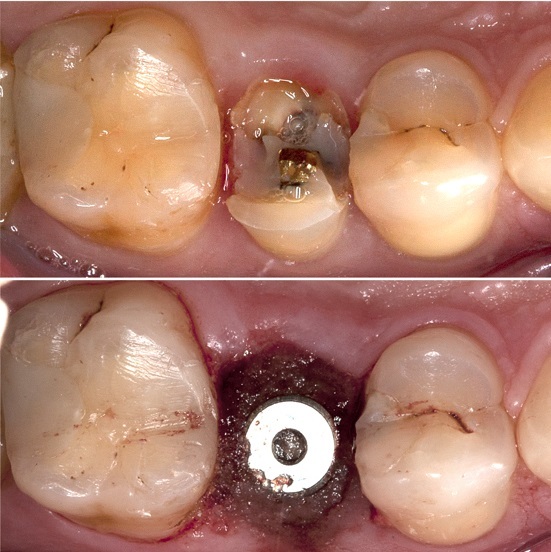

Экспресс-имплантация зубов: фото до и после

Экспресс-имплантация – это процедура удаления зубов и одновременной установки на их место искусственных конструкций. При этом применяются специальные импланты небольшого размера.

2. Установка искусственных конструкций. В кости делается прокол, который будет ложем для импланта. Такая технология исключает травмирование тканей, что способствует быстрому восстановлению.

Эта разновидность одномоментной имплантации зубов предусматривает внедрение титанового штифта в лунку после удаления зуба, но абатмент и постоянная коронка ставятся не сразу, а через несколько месяцев после операции. На период реабилитации на имплант устанавливается временный протез, замену которого производят только после полного приживления искусственной конструкции.